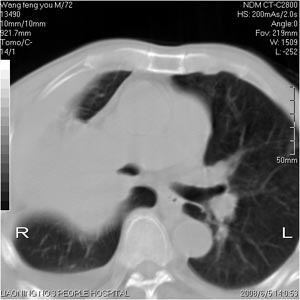

患者:男 72岁 右肩痛半年,近日来咳血,就诊.

右肺中心型肺癌并上叶不张,右侧胸腔积液,做镜检吧.

典型右中心型肺癌并右肺上叶不张,左肺转移,右胸腔积液。

考虑:右肺上叶中心型肺癌伴肺不张、肋骨转移、肩胛骨转移、右侧胸腔积液。

1.考虑:右肺上叶中央型肺癌并右肺上叶不张及右侧多发肋骨、上纵隔淋巴结及左肺转移。

2.右侧胸腔积液。